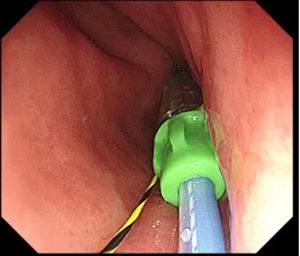

▲ 通过导丝植入支架